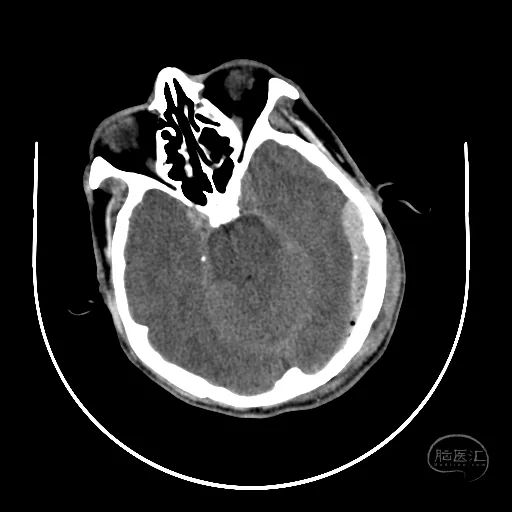

术后18天复查颅脑CT,显示小脑半球恢复良好,第四脑室清晰。

硬膜外血肿基本吸收。

额叶水肿减轻。

脑室稍扩张,骨窗张力较低。

患者GCS评分8分,已转入普通病房,继续康复治疗。